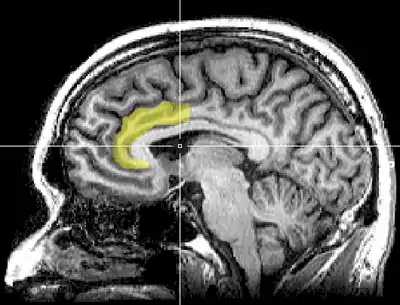

Emotion regulation

Emotions can be regulated cognitively or behaviorally. Cognitive regulation (in terms of mindfulness meditation) means having control over giving attention to a particular stimuli or by changing the response to that stimuli. The cognitive change is achieved through reappraisal (interpreting the stimulus in a more positive manner) and extinction (reversing the response to the stimulus). Behavioral regulation refers to inhibiting the expression of certain behaviors in response to a stimulus. Research suggests two main mechanisms for how mindfulness meditation influences the emotional response to a stimulus.

- Mindfulness meditation regulates emotions via increased activation of the dorso-medial PFC and rostral ACC.[6]

- Increased activation of the ventrolateral PFC can regulate emotion by decreasing the activity of the amygdala.[18][19][20] This was also predicted by a study that observed the effect of a person's mood/attitude during mindfulness on brain activation.[21]

Lateral prefrontal cortex (lPFC) is important for selective attention while ventral prefrontal cortex (vPFC) is involved in inhibiting a response. As noted before, the anterior cingulate cortex (ACC) has been noted for maintaining attention to a stimulus. The amygdala is responsible for generating emotions. Mindfulness meditation is believed to be able to regulate negative thoughts and decrease emotional reactivity through these regions of the brain. Emotion regulation deficits have been noted in disorders such as borderline personality disorder[22] and depression.[23] These deficits have been associated with reduced prefrontal activation and increased amygdala activity, which mindfulness meditation might be able to attenuate.